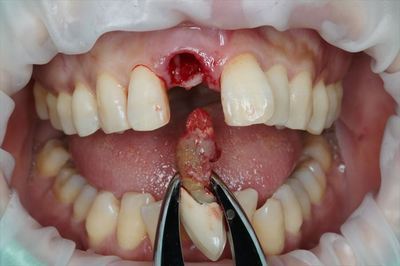

いよいよ本日から治療開始です。

まずは無事に抜歯を終えました。

IMG_9043_R25.JPG

歯根の状況から、歯髄の活性が高い時代に折れて癒合していることが考えられます。

いままでお疲れさまでした、と声を掛けたくなります。